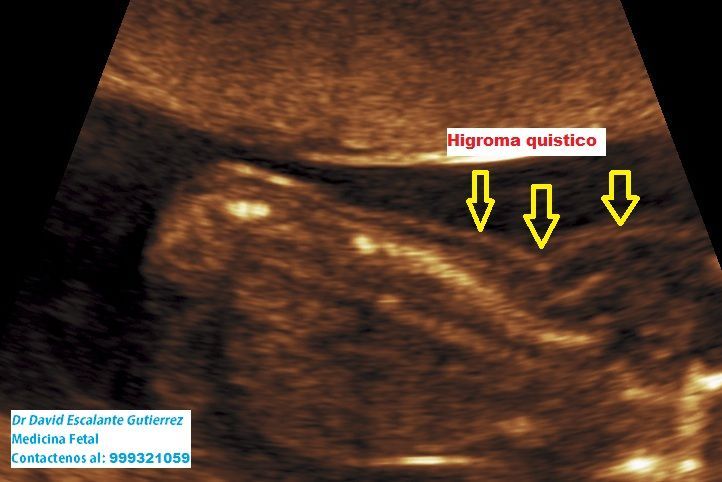

Realizamos las ecografías de viabilidad del embarazo, genética, morfológica, de bienestar fetal, ecocardiografías fetales, así como procedimientos invasivos como biopsia de vellosidades coriales y amniocentesis.